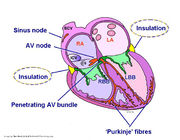

| 10:36, 18 May 2012 | Figure 2.jpg (file) |  |

1.25 MB | 1 | |